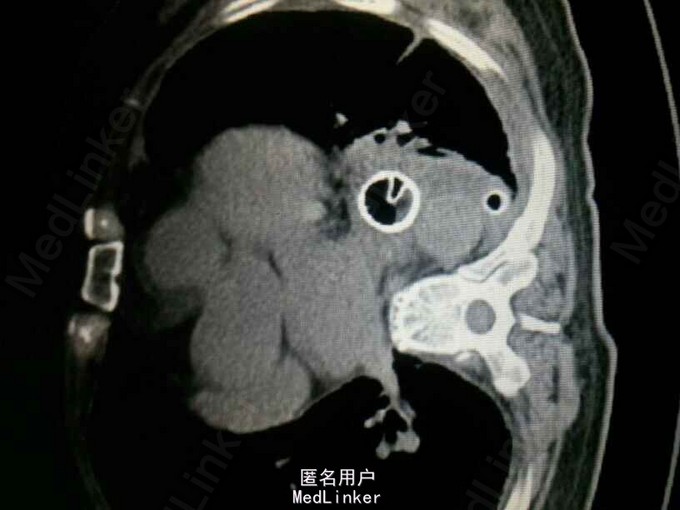

查体:气管居中,左肺呼吸音弱,右肺呼吸音尚可。未闻及湿啰音。胸腔引流管可见褐色浑浊液体引出。 腹部CT肝脾胰未见异常,胆总管扩张。 食管造影:食管下端撕裂,食管胸膜瘘。 胸CT左肺气胸,左侧胸腔内高密度影,考虑造影剂漏入胸腔。左肺实变,右侧少量胸腔积液。

诊断:自发性食管破裂。 治疗:急诊行胸腔闭式引流。后行左剖胸食管破裂修补。术中见胸腔污染严重,见菜叶,消化液等。后纵膈可见较多脓性分泌物,食物残渣,坏死组织。食管裂口处上方可见5cm纵向肌层及粘膜层撕裂口,相应位置处可见纵膈胸膜撕裂口。术后予肠内肠外营养,舒普深,泰能,稳可信,抗感染,术后反复行2次食管造影,仍存在食管破裂口,术后一月行胃镜及食管支架植入术。第二天行进食流质及半流质通畅,平稳出院。